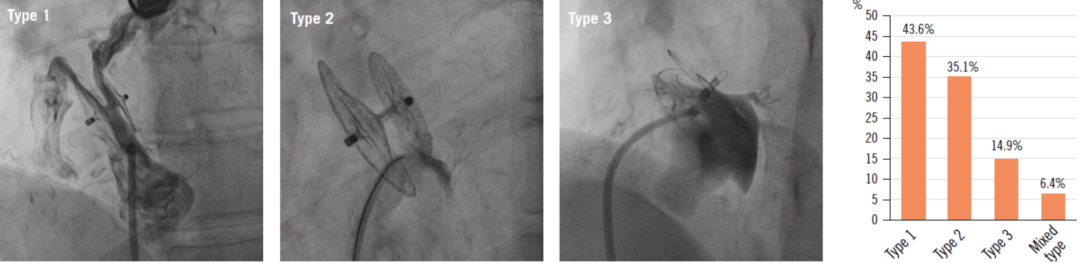

PFO封堵后残余分流发生率较高并且与卒中复发等临床事件高度相关。一项来自捷克的研究通过分析498例因隐源性卒中/TIA接受PFO封堵术患者的长期随访数据(平均5.24年)发现,术后6个月时35%的患者存在残余分流,至12个月时降至19%。与无分流者相比,存在任何等级残余分流患者的卒中/TIA年复发风险增高3.57倍。风险升高主要由大量分流(III级)驱动,风险比为3.71[21]。另一项来自意大利的多中心回顾性研究中,2362例行PFO封堵术的患者中,207例(8.8%)有残余分流,其中材质较硬的封堵器可能更容易出现。右向左分流(RLS)严重程度与复发卒中/TIA/严重偏头痛等症状相关(OR 2.467)。为了便于交流和制定处理策略,根据残余分流发生的部位,将残余分流分为三型:1型:分流在两盘片之间,最为常见,占43.6%;2型:盘片旁分流,占35.1%;3型:1和2型以外的分流,占14.9%(图2)。按照不同分流类型,结合临床表现,可以酌情采用血管塞,封堵器,弹簧圈等不同方法进行二次封堵[22]。

图2. PFO封堵术后残余分流的类型和发生率